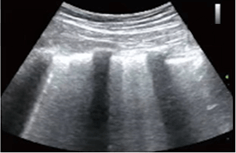

D1.  D2.

Figure D. In image D1, the TE7 Ultrasound machine is looking at the inferior vena cava (IVC). Image D2 shows the lung with ultrasound and D3 shows a cardiac assessment with smart measurements to check heart function. Images courtesy of Mindray Medical International.

Smart Inferior Vena Cava (Smart IVC) – Automated measurement of Inferior Vena Cava (IVC) helps assess volume status and guides fluid management. A trending graph documents the change in collapsibility (CI) and distensibility (DI) to document fluid response over time and guide therapy.

Smart Inferior Vena Cava (Smart IVC) – Automated measurement of Inferior Vena Cava (IVC) helps assess volume status and guides fluid management. A trending graph documents the change in collapsibility (CI) and distensibility (DI) to document fluid response over time and guide therapy.